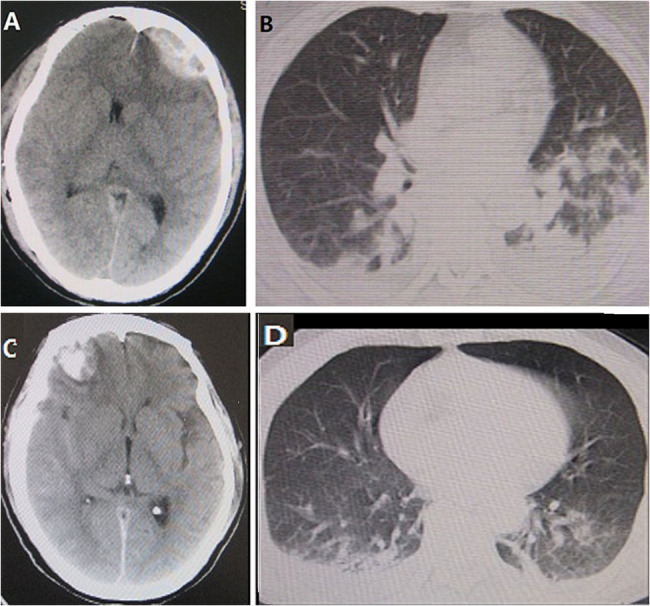

Results: Among a random sample of 412 adult patients with sTBI, we found 249 sepsis after sTBI (60.4%) and 163 (39.6%) non- sepsis after sTBI events. The main organ failure was early brain (94.8%) and lung injury(91.2%) caused by community-acquired pnumonia (CPA). The CT score was higher in the sTBI with sepsis group than in the sTBI without sepsis group(wean 3.5 score vs. 0.9 score, p < 0.001).The SOFA score was also higher in the sTBI with sepsis group than in the sTBI without sepsis group(wean 5.9 score vs. 3.6 score, p < 0.001). The risk of death for sepsis after sTBI was an elevated CT score (hazard ratio[HR], 4.6; 95% confidence interval[CI], 3.373-10.49; p < 0.001) and an elevated SOFA score (HR,3.0; 95% CI, 2.054-4.826; p < 0.001).The area under the ROC curve for mortality was significantly larger for the elevated CT score (0.90, 95%CI 0.86-0.97 ) than for the elevated score (0.85, 95%CI 0.81-0.89 ) (P < 0.001). The elevated CT score in the area under the ROC curve for mortality was with 97.0% of sensitivity and 100.0% of specificity. At 60 days follow-up, the risk of death for sepsis after sTBI was higher than those non- sepsis after sTBI (p < 0.001).

Conclusions: Elevated CT score is a well indicator of high incidence and mortality for sepsis after sTBI in the ICU, which suggests that this very current and practical event is involved to a global health care problem. But it could still need further verification in future investigation.